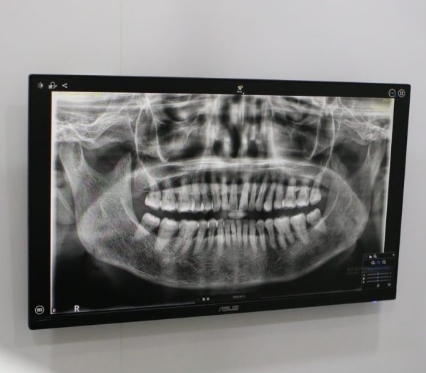

作為設備完善的荔枝角診所,林宇軒牙科診所配備多項先進儀器,包括平面全口 X 光(OPG)、電腦斷層掃描(CBCT)及口腔掃描儀,能夠精準診斷牙齒、牙周及牙根狀況,為各類治療提供可靠依據,提升治療成效與安全性。